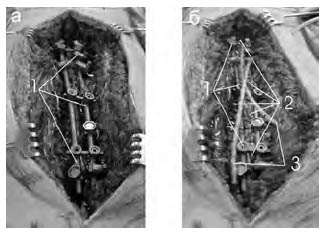

На рис. 7 представлен один из типичных интраоперационных вариантов смонтированной конструкции BelCD при операции по поводу сколиотической деформации позвоночника, сопровождающейся дорсальным спондилодезом костными трансплантатами и установкой тренажной системы.

Рис. 7. Интраоперационные фрагменты имплантации конструкции BelCD: а – завершение монтажа, б – уложены костные аутотрансплантаты и установлены дренажные трубки; 1 – собранная конструкция, 2 – костные трансплантаты, 3 – дренажные трубки